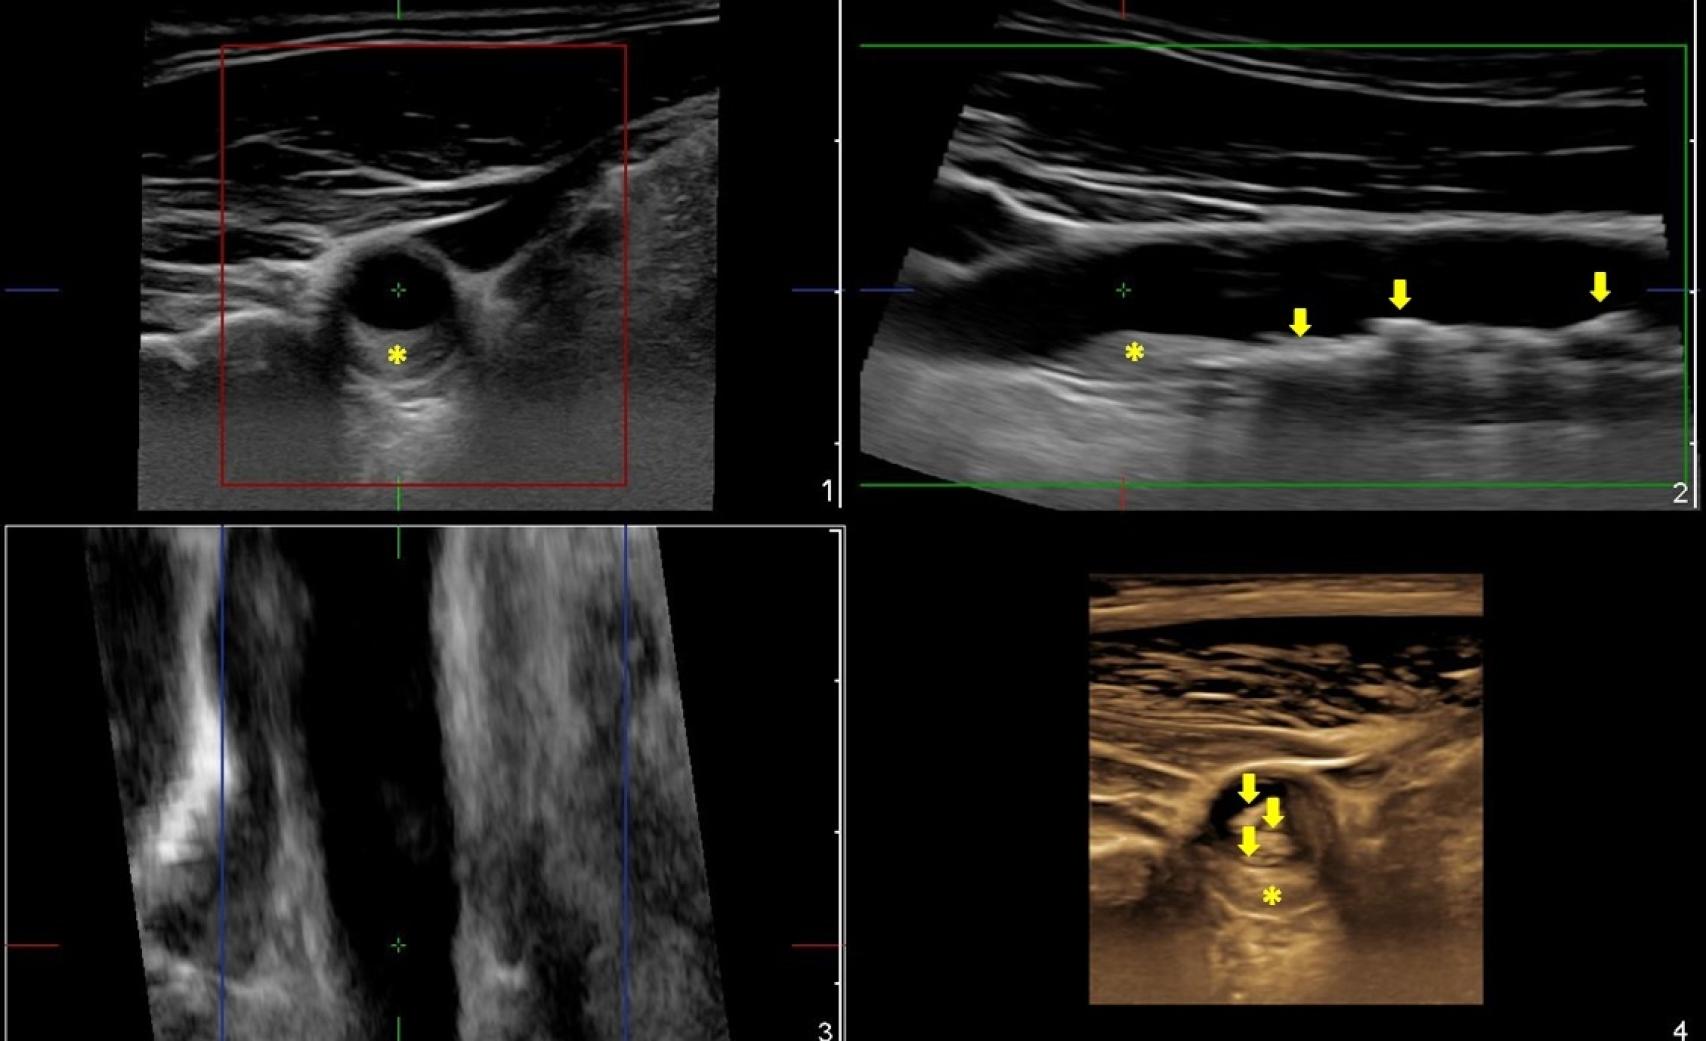

En este caso se aprecia una extensa afectación por aterosclerosis observándose varias lesiones, una primera placa (Foto 1) que ocasiona en mayor medida la obstrucción de la luz del vaso, y varias placas indicadas con flechas (Foto 2) que, no siendo obstructivas, son las más extensas. En la imagen en 3D (Foto 4) se pone de manifiesto cómo podemos valorar la presencia, disposición, extensión y grado de obstrucción de todas las placas, lo que nos da una idea más precisa del daño por aterosclerosis en un único estudio. (Valoración de la Dra. Beatriz López Melgar).

En este caso se aprecia una extensa afectación por aterosclerosis observándose varias lesiones, una primera placa (Foto 1) que ocasiona en mayor medida la obstrucción de la luz del vaso, y varias placas indicadas con flechas (Foto 2) que, no siendo obstructivas, son las más extensas. En la imagen en 3D (Foto 4) se pone de manifiesto cómo podemos valorar la presencia, disposición, extensión y grado de obstrucción de todas las placas, lo que nos da una idea más precisa del daño por aterosclerosis en un único estudio. (Valoración de la Dra. Beatriz López Melgar). HM Hospitales